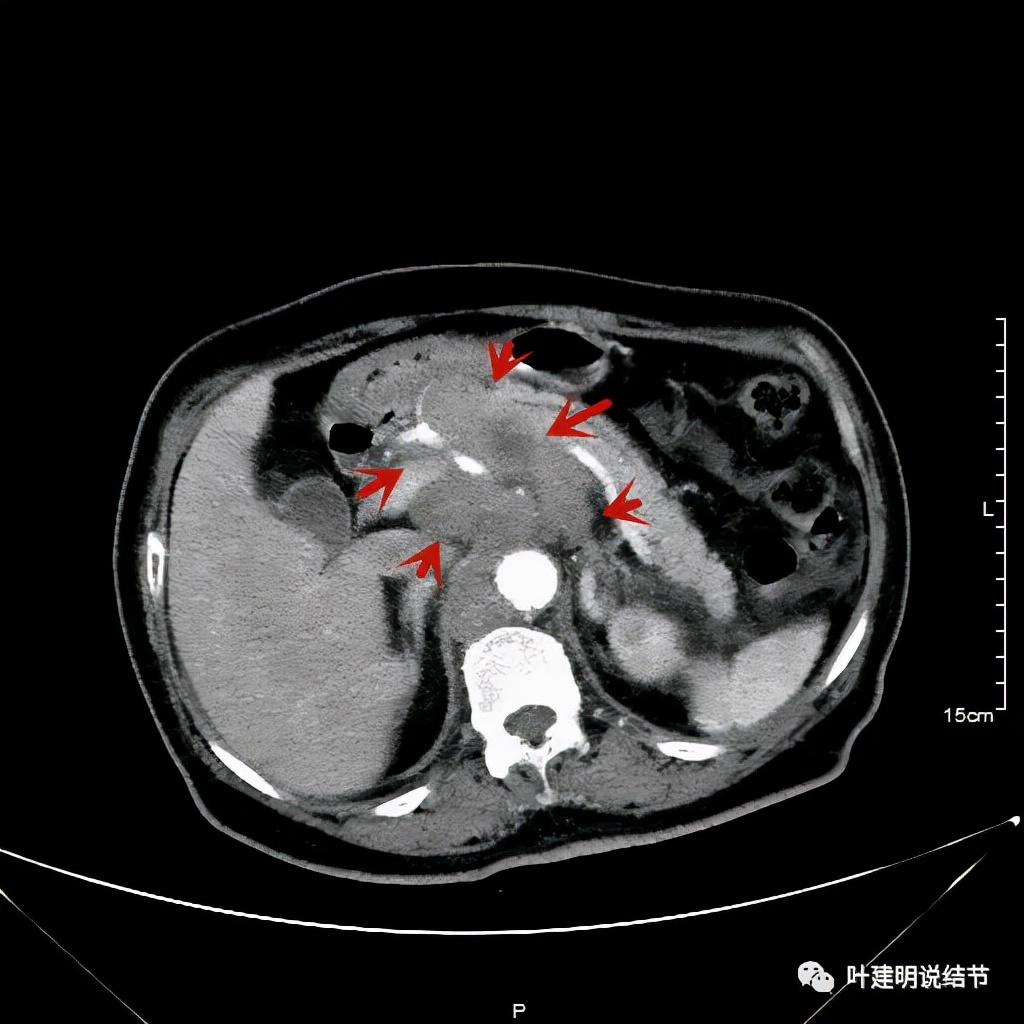

其实胸部CT示食管的病变感觉并不厉害,外侵或纵隔内转移均不明显,但其腹部的CT让人大吃一惊!

上图是初发现时的CT影像报告,其他CT图像上红色箭头所指范围内都是肿瘤,整合成团,挤压血管以及正常器官结构。你有见过原发灶这么不显眼,而腹部转移灶这么厉害的食管癌吗?但经过穿刺证实是转移性鳞癌,结合病史考虑是食管癌转移。手术自然是不可能了根治了,放疗也不合适,经过MDT并与患方充分沟通,依据食管癌治疗指南: